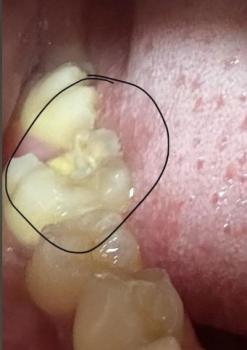

This image shows a patient undergoing orthodontic treatment with fixed braces. A small, localized ulcerated lesion is visible on the inner cheek, clearly marked. The lesion is positioned directly adjacent to orthodontic brackets and wire, suggesting mechanical irritation from braces as the primary contributing factor.

Small round ulcer on inner cheek mucosa

Pale or whitish center with surrounding redness

Mild local swelling

Orthodontic hardware in direct contact with lesion

No visible pus or active bleeding

Findings are consistent with a traumatic oral ulcer

Likely caused by repeated friction from braces during chewing or speaking

Orthodontic appliance–related traumatic ulcer

Localized oral mucositis